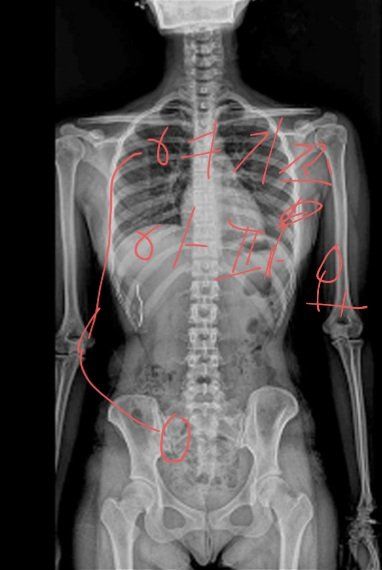

(엑스레이사진은 제것이 아니에요)

병원가서 엑스레이 찍고 일자허리에 4번척추에 디스크 약간 있다고 했어요. 또 결과 사진에 이런거 비슷한거 있었어요

(위에 사진)

방향은 맞는지 모르겟어요

도수치료랑 진통제처방 해주셨어요 엑스레이 찍었을 때 척추가 특이한게 이랬어요